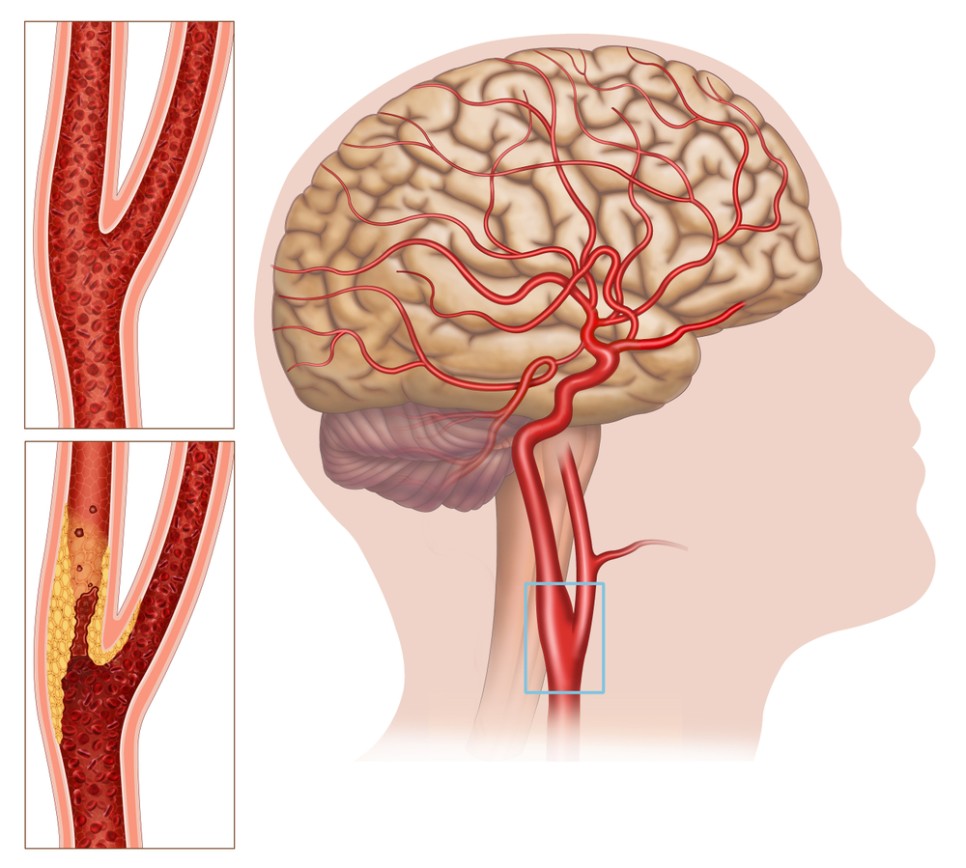

뇌로 가는 혈액의 80%를 보내는 목에 있는 중요한 혈관으로 경동맥경화가 진행되면 뇌졸중 발생 위험이 높아지기 때문입니다. 경동맥에 생긴 찌꺼기가 뇌혈관으로 흘러 들어가 뇌혈관을 막을 확률이 높아집니다.

경동맥이 막히는 질환을 ‘경동맥협착증’이라고 합니다. 허혈성 뇌졸중 원인의 30%를 차지할 정도로 우리 생활에 바짝 다가선 경동맥협착증.

경동맥협착증은 혈관벽의 병변으로 경동맥이 좁아지는 동맥경화증, 동맥벽이 찢어지고 박리되는 경동맥박리증, 큰 동맥 여러 곳에 일어나는 만성혈관염증은 고곡수동맥염 등이 있습니다.